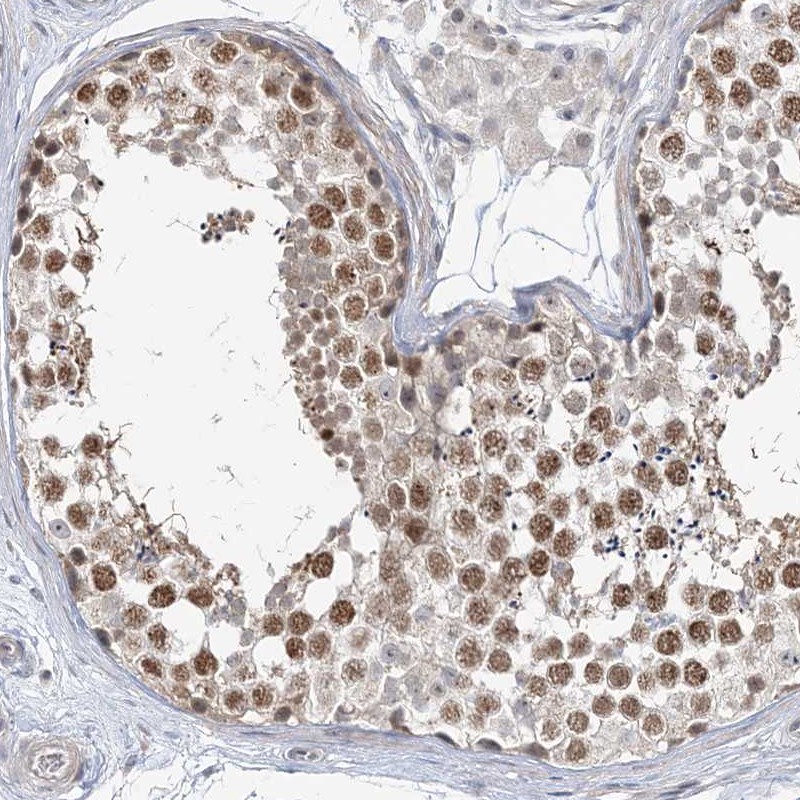

Immunohistochemical staining of human testis shows moderate nuclear positivity in cells in seminiferus ducts.